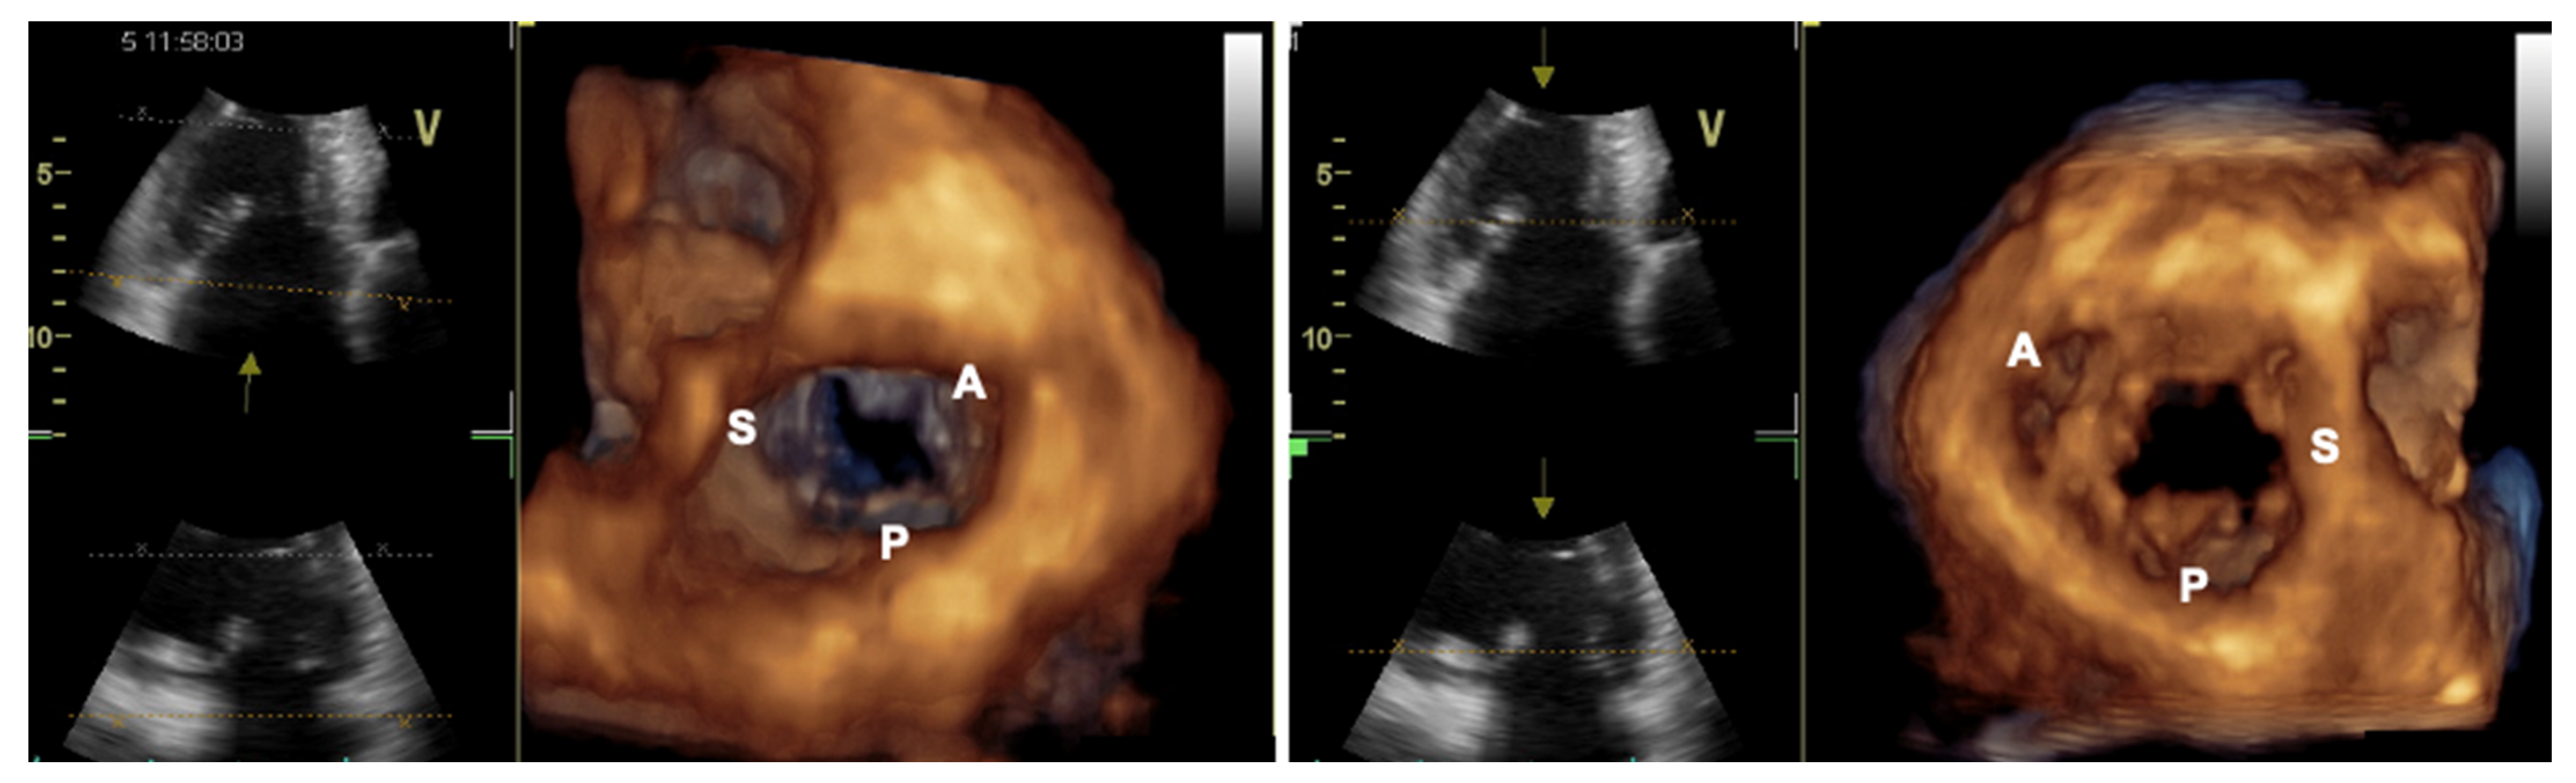

- Ancona, F.; Stella, S.; Taramasso, M.; Marini, C.; Latib, A.; Denti, P.; Grigioni, F.; Enriquez-Sarano, M.; Alfieri, O.; Colombo, A.; et al. Multimodality imaging of the tricuspid valve with implication for percutaneous repair approaches. Heart 2017, 103, 1073–1081. [Google Scholar] [CrossRef] [PubMed]

- Agricola, E.; Ancona, F.; Stella, S.; Rosa, I.; Marini, C.; Spartera, M.; Denti, P.; Margonato, A.; Hahn, R.T.; Alfieri, O.; et al. Use of Echocardiography for Guiding Percutaneous Tricuspid Valve Procedures. JACC Cardiovasc. Imaging 2017, 10, 1194–1198. [Google Scholar] [CrossRef]